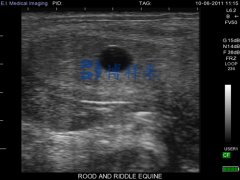

表明母牛胎体生存能力的一个必要特征是胎儿液体的无回声性质。在第 10 天到第 50 天之间,高达 15% 的妊娠发生胚胎死亡。……